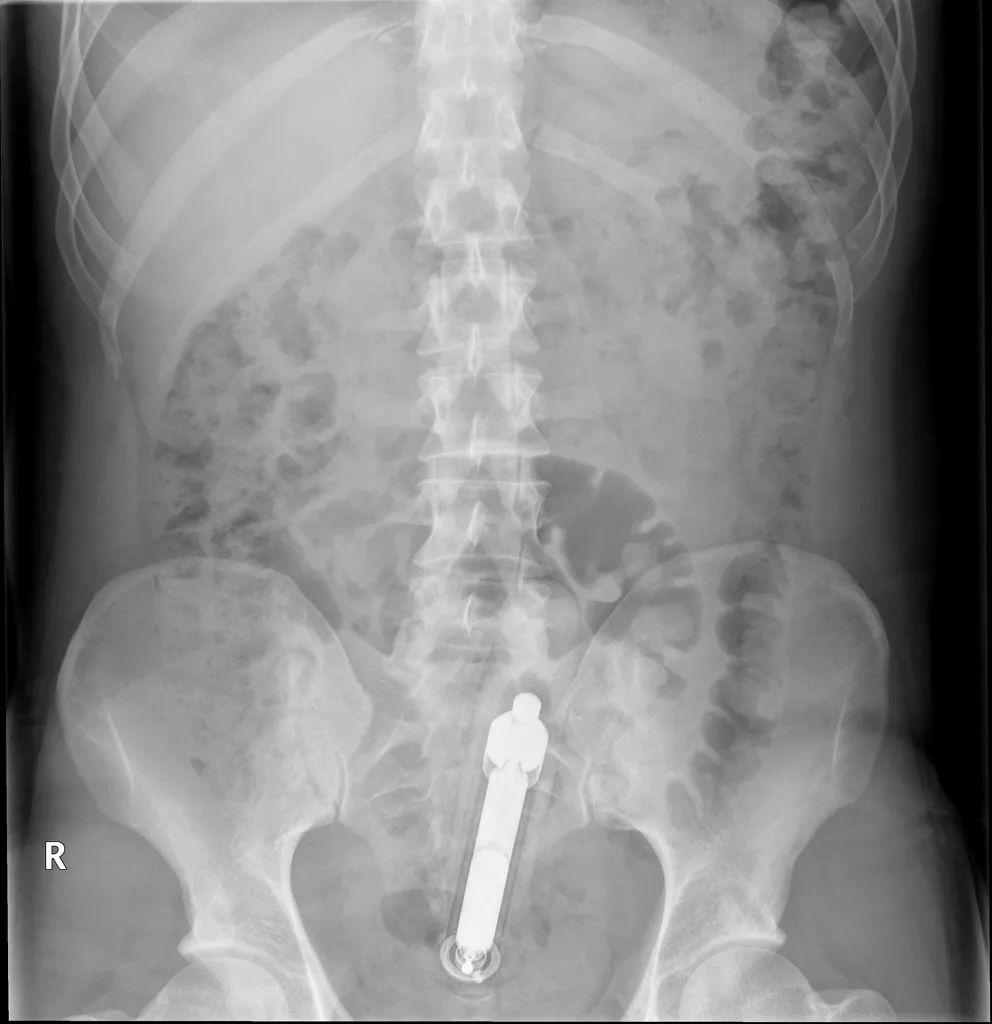

06 一把拧开了错误之门的螺丝刀具的故事

在一份丹麦语的医学杂志上,几名医生报告了一例58岁男子臀部肿胀的案例。最终医生们发现这是因为他把电动螺丝刀插入了自己的直肠导致的。

取出异物后这个人成功获救了,但他很快离开了医院。医生们一致认为,“出于某些禁忌的原因,患者就诊后的相关咨询可能不够充分”。如果有什么建议的话,医生们只想说“非熟练工的第一次不要乱尝试用电动工具啦”。